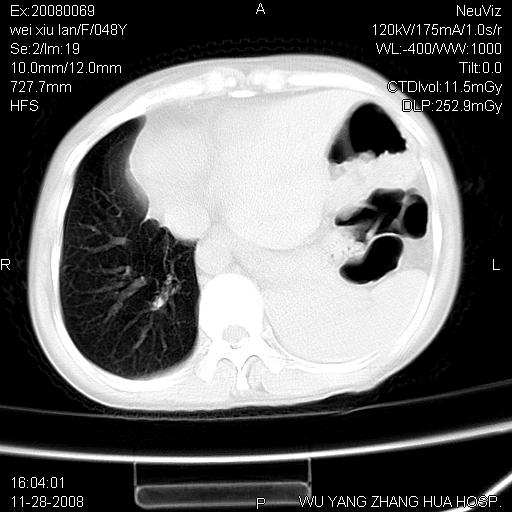

标题: CT16847:女,48岁,咳嗽,发热两日,平常偶有上腹部不适。 [打印本页]

标题: CT16847:女,48岁,咳嗽,发热两日,平常偶有上腹部不适。

能否考虑食管裂孔疝?请老师们多多指教。

这个是左侧膈膨升伴不完全性胃翻转,手术将松弛的左横膈膜折叠缝合即解决问题。

支持左侧膈疝,心脏受压右移.

胃、脾脏及部分肠管明显升高,并压迫心脏移位,

首先考虑:左侧膈疝。

左侧胸腔内见胃肠及脾脏影

支持膈疝

左膈顶及肋膈角均上移,膈面光滑,考虑左膈肌麻痹